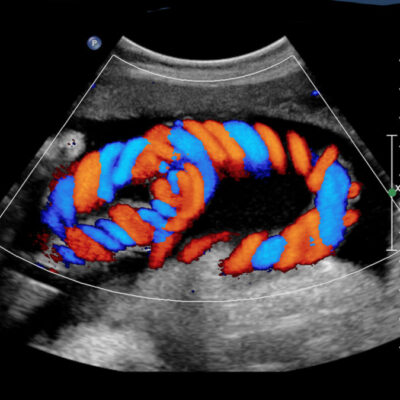

Fetal Growth & Doppler Scan

Monitors fetal growth, amniotic fluid, placental position, and blood flow in the baby and mother, helping identify growth issues or complications.